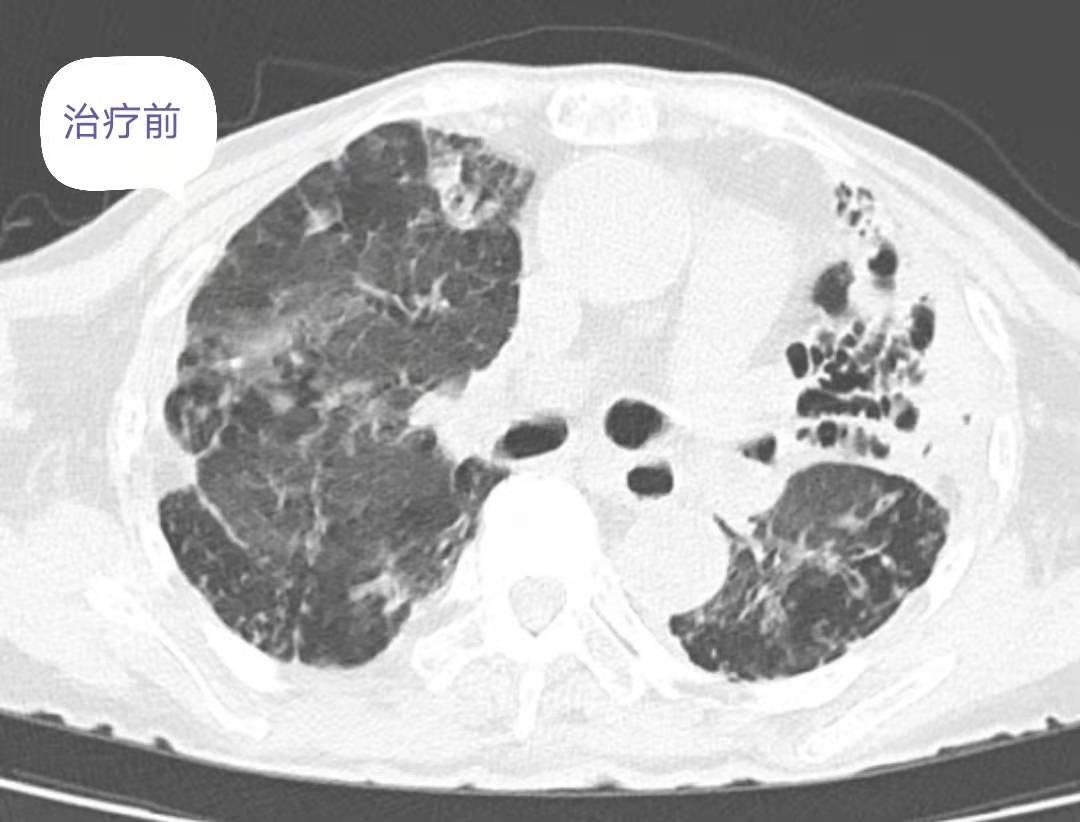

非结核分枝杆菌肺病的综合分析报告

进行性系统性硬化症(PSS)

进行性系统性硬化症(PSS)又称系统性硬化,是一种以皮肤纤维化为主,并累及血管和内脏器官的自身免疫性疾病。病变呈局限性良性皮损,称为硬皮病;有广泛的皮损,并累及内脏器官,称为弥漫性...